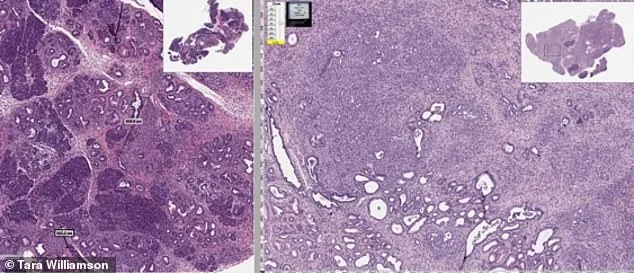

The image shows two mice genetically prone to developing pancreatic cancer. The untreated mouse developed tumors (LEFT), while the mouse that was given the drug mebendazole in its diet showed little or no signs of cancer. In addition to brain tumors, the researchers suggest the drug could potentially be studied as a therapy for a wide range of cancers, including those affecting the breast, lung, pancreas, colon, liver, prostate and blood. Interest in the patent has grown in recent days after a decades-old intelligence document began circulating widely online.